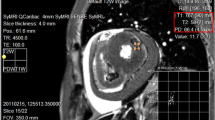

Myocardial infarct (MI) size has been increasingly used as an endpoint in multiple clinical trials and has thus become an important clinical measure. While late gadolinium enhancement MRI is considered the clinical reference standard to detect, characterize, and quantify MI, there is no established universal quantification algorithm that provides reliable MI assessment in every scenario. Efforts have been made to improve the binary threshold-based methods which dichotomize MRI voxels as either healthy or infarcted. Novel algorithms have also been proposed to quantify the actual infarcted tissue content of each MRI voxel while accounting for partial volume averaging, a common issue in quantitative MRI. Currently, the full-width at half-maximum binary algorithm seems to have the highest accuracy and reproducibility. Non-binary algorithms show comparable results; however, the literature is limited in terms of their clinical feasibility.